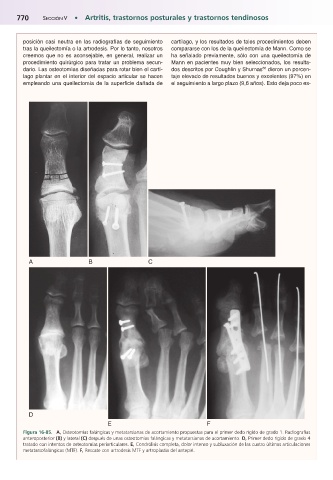

Figura 16-85.mA, Osteotomías falángicas y metatarsianas de acortamiento propuestas para el primer dedo rígido de grado 1. Radiografías

anteroposterior (B) y lateral (C) después de unas osteotomías falángicas y metatarsianas de acortamiento. D, Primer dedo rígido de grado 4

tratado con intentos de osteotomías periarticulares. E, Condrólisis completa, dolor intenso y subluxación de las cuatro últimas articulaciones

metatarsofalángicas (MTF). F, Rescate con artrodesis MTF y artroplastia del antepié.